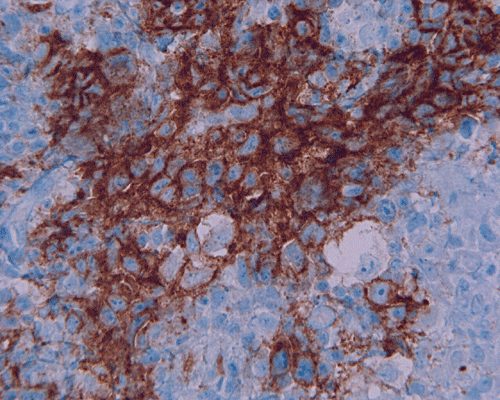

Paraffin sections: The entire volume of the tissue is made up of a granulomatous inflammation with poorly formed granuloma (Panel F, G, and H). The density of the lymphocytes is variable in different areas. In some areas, there is a rather intense lymphocytic infiltration accompanied by scant atypical cells with enlarged nulcei and prominent nucleoli (arrows in Panel I and J, Panel J is a higher magnification of Panel I). These atypical cells are quite easy to be missed. No microorganisms were identified by acid fast stain, PAS stain or GMS stain. The lymphocytes but not the atypical cells are positive for CD20 (Panel K) or CD3 (Panel L). The granulomatous background is strongly positive for CD68 (Panel M). Only rather faint positive staining for placental alkaline phosphatase (PLAP) is demonstrated and the interpretation is difficult as they are present in areas with crush artifact (Panel N). Many of the large, atypical cells are positive for CD117 (c-kit) (Panel O).

Immunohistochemically, the neoplastic cells show cytoplasmic membranous patten, sometimes diffuse cytoplasmic pattern, of staining for placental alkaline phosphatase (PLAP). Detection of c-kit (CD 117) in germinoma has been demonstrated and serves as a good diagnostic aid. Activating KIT mutations may contribute to tumorigenesis in germinoma 6, 7, 8. Syncytiotrophoblastic cells can be positive for human chorionic gonadotrophin (hCG). Occasional positive immunoreactivity for cytokeratin has been described and should not be taken as the sole evidence for embryonal carcinoma.